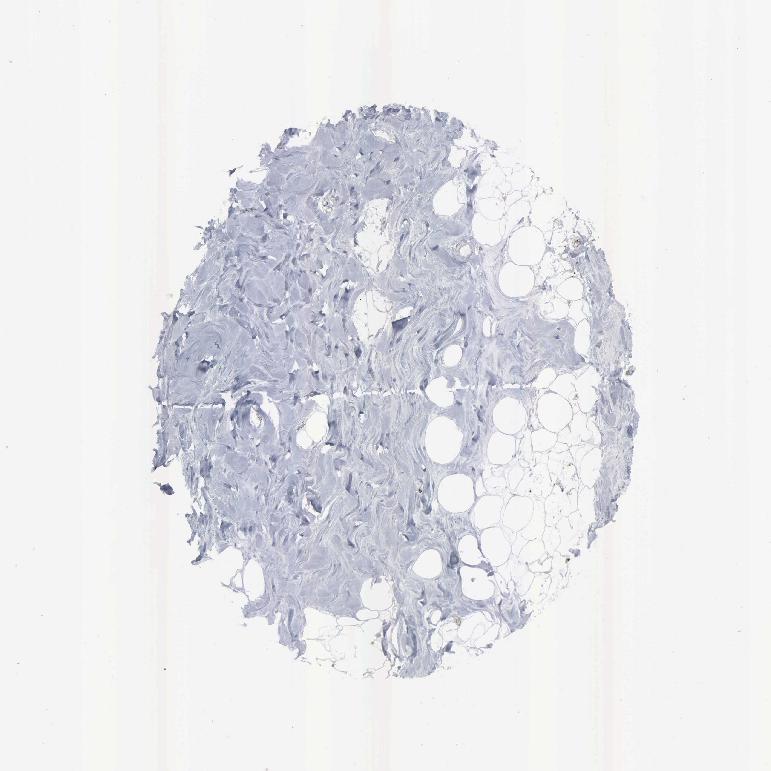

SOFT TISSUE 2 - Antibody stainingi

Antibody staining in the annotated cell types in the current human tissue is reported as not detected, low, medium, or high, based on conventional immunohistochemistry profiling in selected tissues. This score is based on the combination of the staining intensity and fraction of stained cells.

Each image is clickable and will lead to virtual microscopy that enables deeper exploration of all samples and also displays staining intensity scores, fraction scores and subcellular localization as well as patient and tissue information for each sample.

Antibody HPA000898Antibody CAB005219

Fibroblasts MediumMedium

Peripheral nerve High-